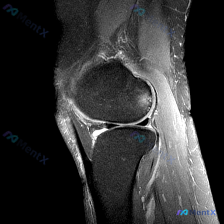

最近看到一份膝关节MRI读片需求,初始焦点指向「软骨异常」,整理了完整的分析思路分享给大家。 基本影像信息 这是一张膝关节MRI矢状位脂肪抑制序列(FS-T2/PD-FS)图像,信噪比、对比度良好,无明显运动伪影,定位为:右侧是前(髌骨侧),左侧是后(腘窝侧)。该序列液体呈高信号,骨髓脂肪信号被抑制...